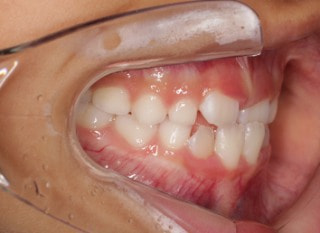

治療前

前歯装置装着時